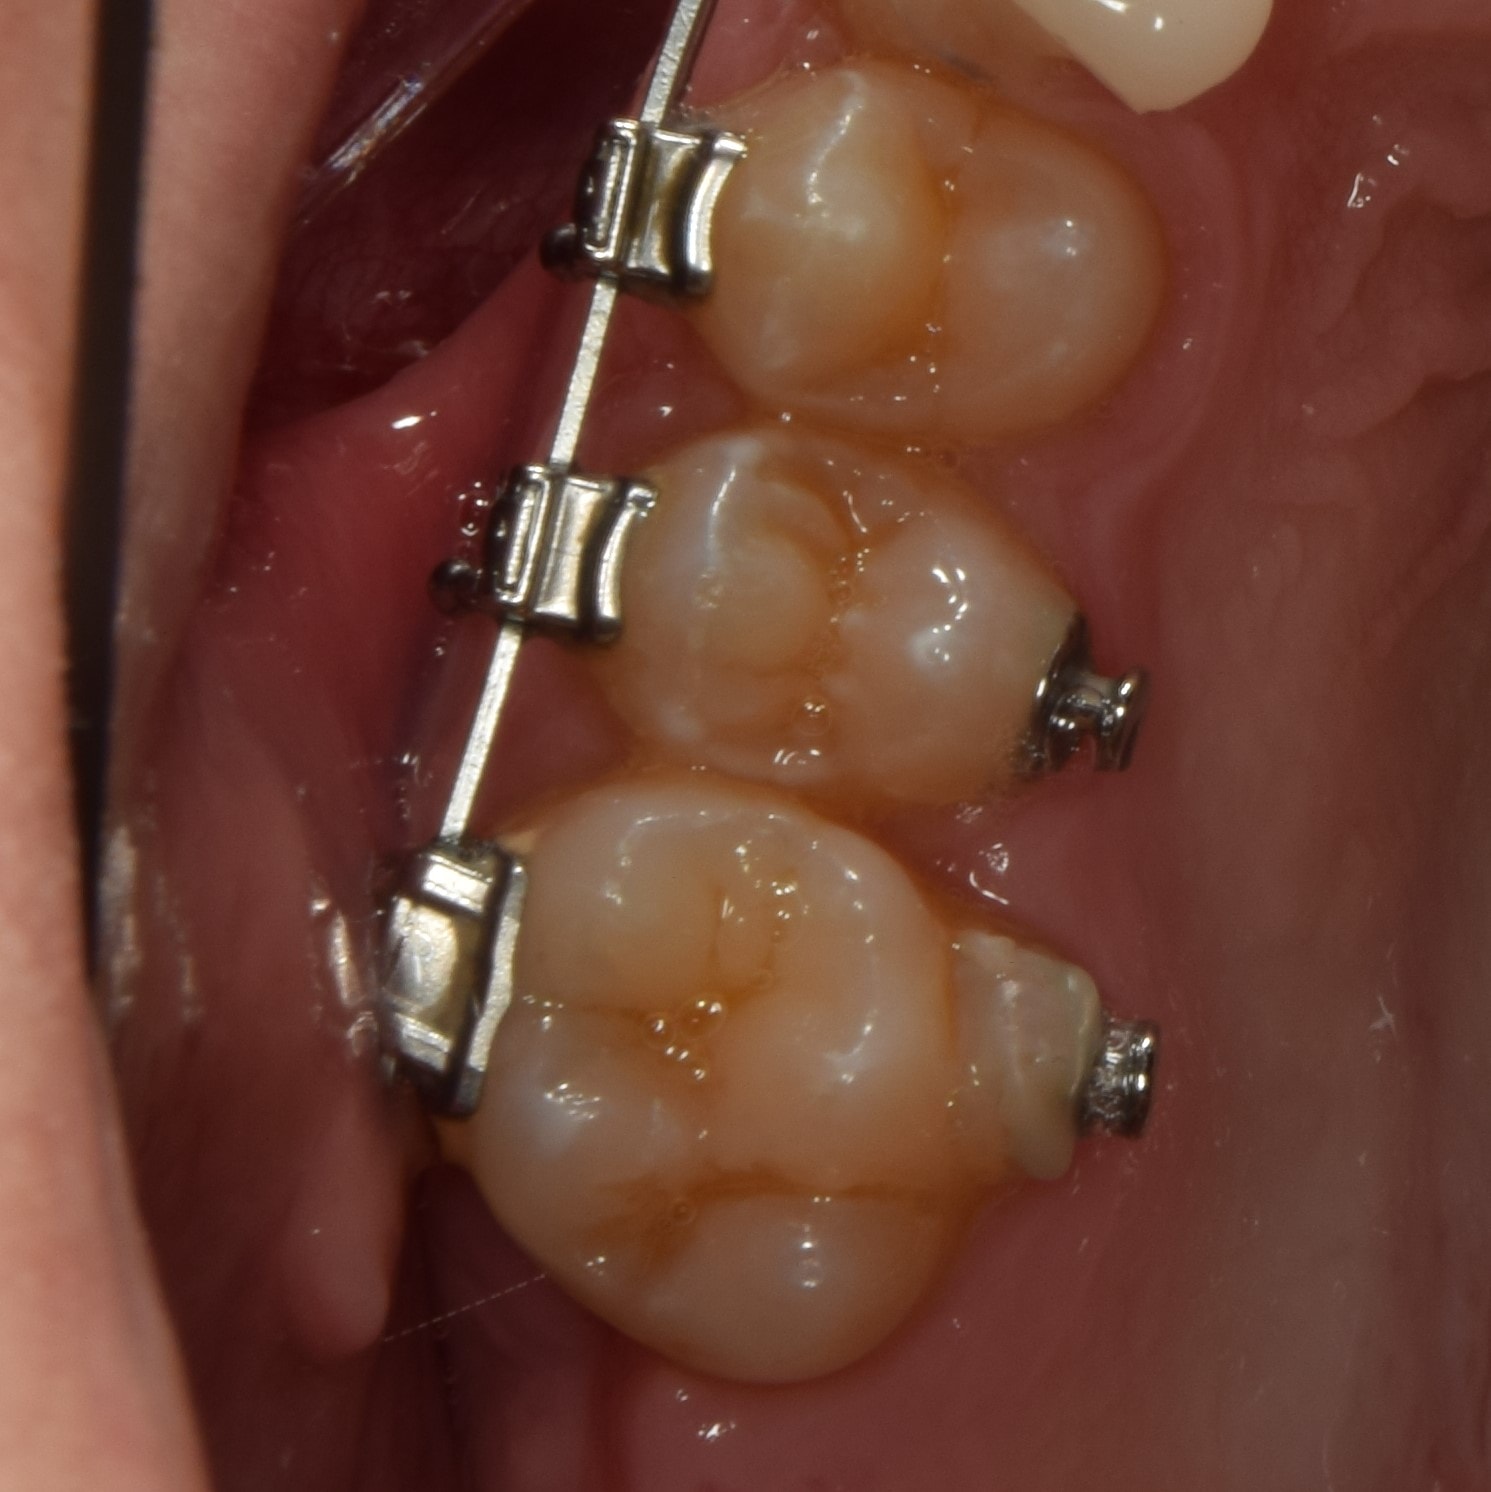

Gyűrű

Általában őrlőfogaknál használt, a teljes fogat körülölelő fém fogszabályzó alkotóelem, melyre tubus van hegesztve. Vannak olyan rögzített (EVA-platte) és kivehető (lip-bumper, Headgear) készülékek, amelyek használatához elengedhetetlen. A fogágyra igen negatív hatással van, ezért használatát minimálisra csökkentettem, de amikor szükséges, jó szolgálatot tesz.

Tubus

Tubusoknak nevezzük a nagyőrlőkre ragasztott rögzített fogszabályzó alkotóelemeket. Nevükben is benne van, hogy egy kis “alagutat” foglalnak magukba, ebbe lehet az íveket belecsúsztatni. A tubusokat általában nem lehet kinyitni, mint a bracketeket, néhány kivételtől eltekintve (önligírozó tubusok, konvertálható tubusok).